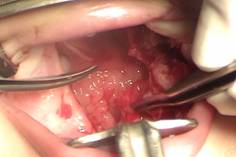

3. Como se trata de una hendidura amplia no se puede pretender hacer una z-plastia de la mucosa nasal, por lo cual se debe cortar junto con la inserción anómala de los músculos del paladar. De esa manera el paladar se va hacia atrás. (Fig. 5 y 6).

Figuras 5 y 6: Momento en que se está cortando la mucosa nasal y el músculo a nivel de su unión con el paladar duro. De esa manera sí se alarga el paladar.